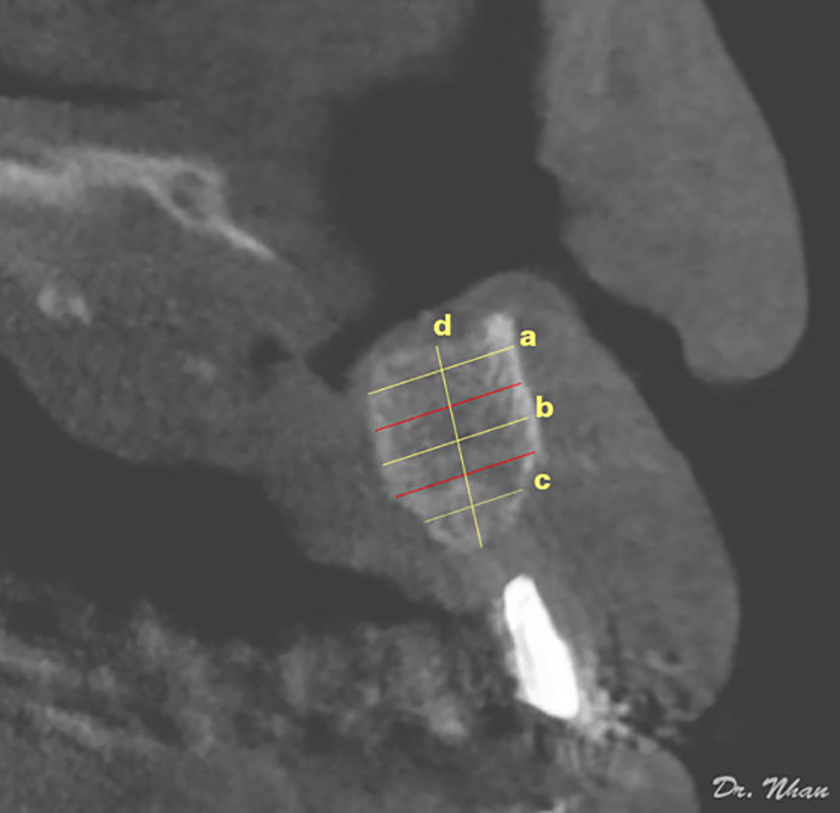

A radiopaque marker (Gutta-percha) was placed vertically along the potential axis of the final restoration, and cone-beam computed tomography (CBCT) scans were obtained with the surgical stent in place. The images were imported into an imaging program (EasyDent V4 Viewer; Vatech, Suwon, Korea) to measure graft dimensions suitable for implant placement. Height was recorded from the lowest point to the highest point of the graft (d in Figure 4). Width was calculated by averaging the buccolingual measurements of the coronal, middle, and apical one-thirds of the graft (c, b, and a, respectively, in Figure 4). Assuming that standard implants of 10 mm length would be biomechanically sound in the lateral incisor region, grafted bone of at least 7 mm height and 4 mm width was required for implant placement. Implant health was evaluated by the Misch et al. (2008) criteria through 4 clinical groups. The successful and satisfactory survival groups showed no pain or tenderness during function, no mobility, and no history of exudate; on radiographs, the crestal bone showed a loss of <2.0 mm in the former group and from 2 to 4 mm in the latter group. However, the group with compromised survival may have sensitivity and history of exudates, but no mobility; on radiographs, this group showed bone loss >4 mm (less than half the length of the implant). In the failure group, all of the following were observed: pain during function, mobility, uncontrolled exudate, and radiographic bone loss more than half the length of the implant or loss of the implant.

Figure 4. Radiographic assessment of grafted bone: height and width measurements on an axial computed tomographic slice.